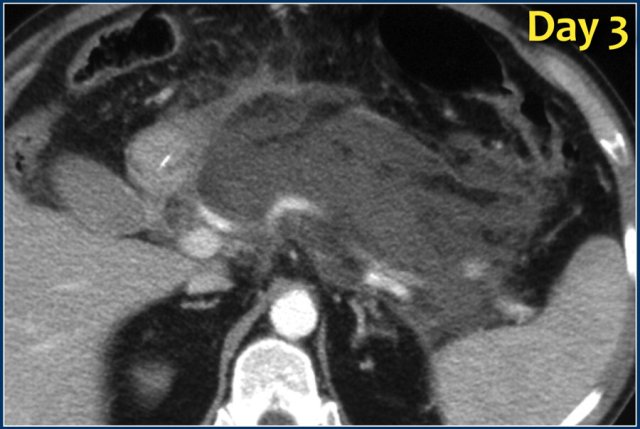

The images show a normally enhancing pancreas on day 1.

As the patient's condition worsened, a second CT was performed on day 3.

Notice how the greater part of the pancreatic body and tail no longer enhances indicating necrotizing pancreatitis (arrows).

The first CT underestimated the severity of the pancreatitis.

This patient died on day 5 due to severe SIRS and multiple organ failure.